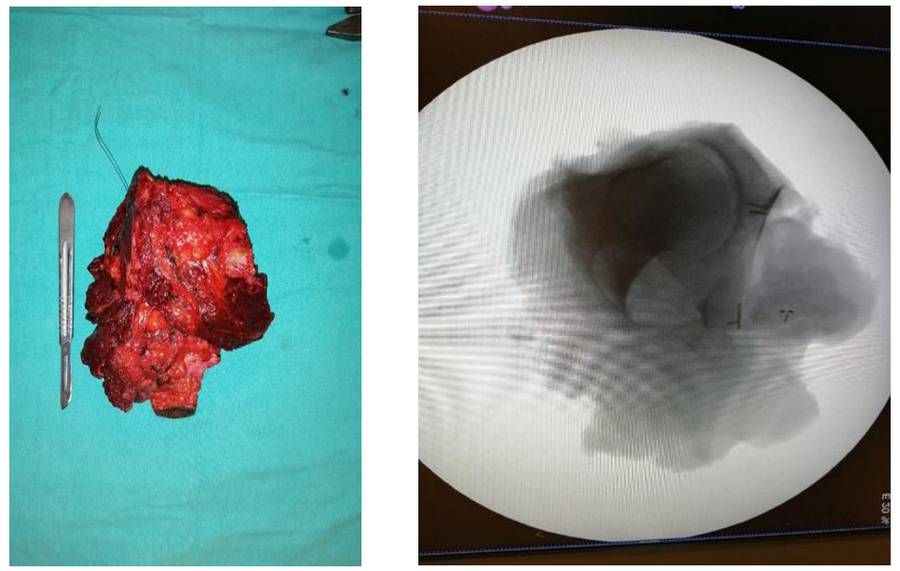

During the operation: The image shows the cavity created after tumor removal, the removed tumor tissue, and the implanted prosthesis.

During the operation: The clinical and radiological images of the removed tumor tissue are shown.